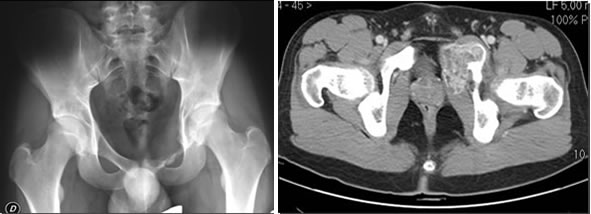

La sintomatologia è di solito rappresentata da tumefazione e dolore, peraltro di grado lieve, la struttura ossea interessata assume un aspetto osteolitico marcato, talora rilevante, le fratture patologiche sono rare.

Le suddette lesioni presentano una ipervascolarizzazione patologica rifornita da uno o più vasi e sono caratterizzate dalla presenza di cavità incluse ripiene di detriti cellulari e sangue, separate da setti connettivali, sono tipici i livelli liquidi ben visibili alla TC ed alla RM.

Adolescente di 16 anni.